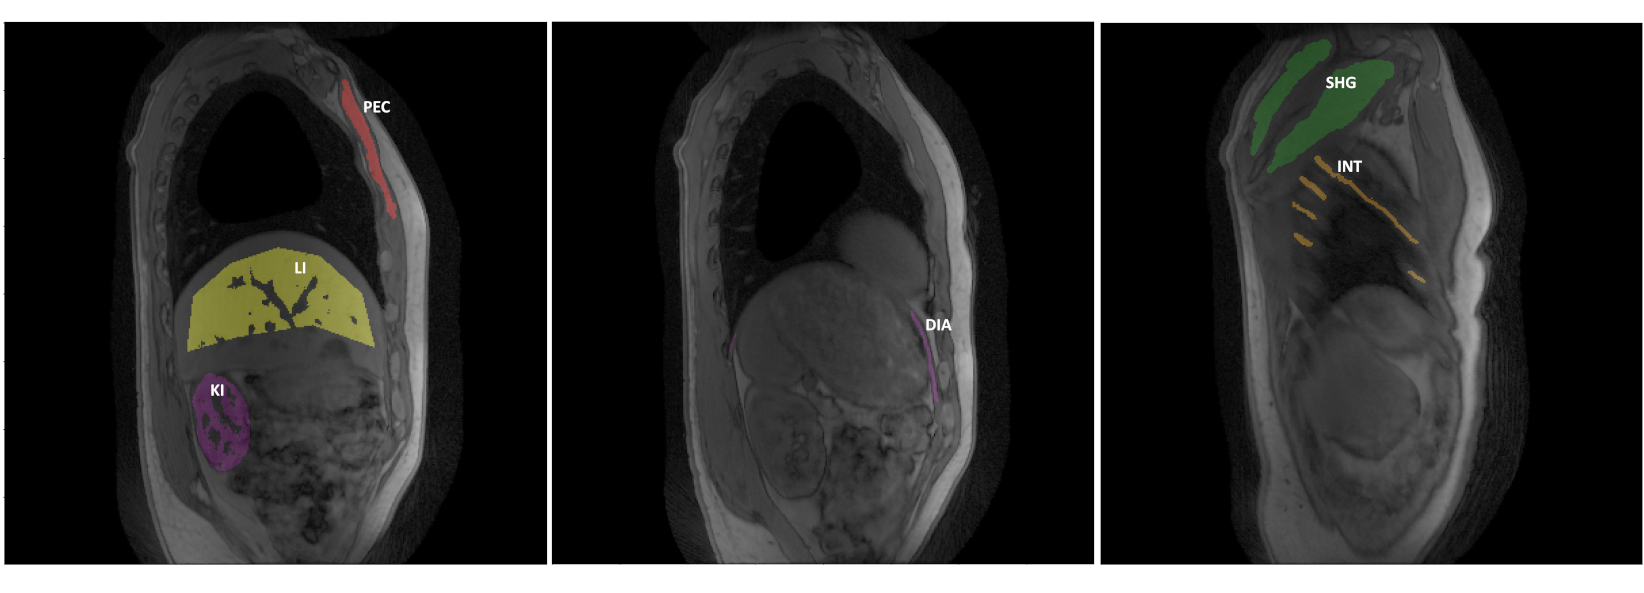

MoCo MRF T1-FF singular volumes and T1H2O𝑇subscript1𝐻2𝑂T1_{H2O} and FF quantitative maps were initially assessed visually against 3D MRF T1-FF (Uncorrected MRF T1-FF), which reconstructs the Singular Volumes using a non-uniform Fourier Transform (nuFFT) [39, 40] on all the acquired data without any binning or motion correction. B0, B1 and T1Fat𝑇subscript1𝐹𝑎𝑡T1_{Fat} parametric maps were also compared (Fig. S4). Manual drawing of Regions of Interest (ROIs) was also performed in several muscles or muscle groups, namely the shoulder girdle (SHG), intercostal muscles (INT), Pectoralis major (PEC), diaphragm (DIA), as well as in the liver (LI) and kidney (KI) (Fig.3). To quantitatively evaluate the accuracy and precision of the resulting quantitative maps, the distributions of T1H2O𝑇subscript1𝐻2𝑂T1_{H2O} and FF values within each ROI were assessed and mean and standard deviations calculated. Since muscles like SHG, INT, and PEC are minimally affected by breathing motion, they were discernible in images obtained without MoCo. This allowed us to compare the ROI-level means and standard deviations of T1H2O𝑇subscript1𝐻2𝑂T1_{H2O} and FF values with and without MoCo in these muscles to evaluate the potential bias on the resulting MoCo MRF T1-FF parametric maps. On the other hand, for muscles and organs significantly impacted by motion such as DIA, KI, and LI, ROIs could only be drawn consistently on MoCo MRF T1-FF images.

Refer to caption

Figure 3: Illustrative example of manual drawing of the different regions of interest for 3 sagittal slices of the motion scan in a healthy subject: Diaphragm (DIA), Intercostal muscles (INT), Kidney (KI), Liver (LI), Pectoralis major (PEC), Shoulder girdle (SHG)